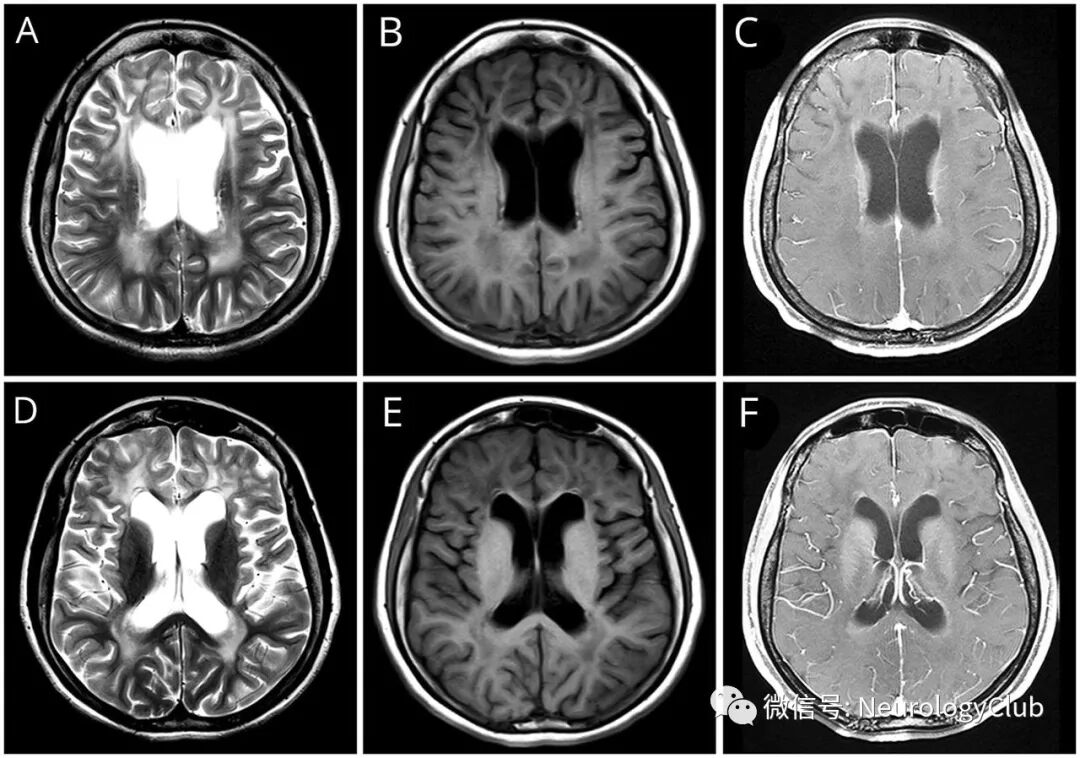

(图1:T2WI[A]和T1WI[B]可见额叶受累为主的脑白质病变,脑室边缘呈T2低信号和T1高信号;增强T1[C]可见脑室周围区域对称强化;T2WI[D]和T1WI[E]可见基底节和脑室旁白质的信号改变,侧脑室前角尖端周围有局灶性靶样病变;增强T1[F]可见基底节病灶强化;这些影像学发现提示I型亚历山大病)